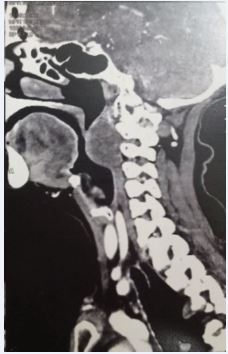

71-year-old women consulted with medial dysphagia during 13 months. She reported a foreign body sensation and actually the perturbance was important and imposed a modification of food ingrain (liquid foods). The global status of this patient is good (memory, hemodynamic constants, cardiac and renal functions). She reports an amigrissement of 8 kg without perturbance (asthenia). Clinical exam revealed a 5 X 4 cm mass in the posterior part of oropharyngeal way. Mucous was well without ulceration. Palpation was not pulsate and not painful. Fibroscopy not shows a nasopharyngeal or hypo pharyngeal extension. The lesion was strictly medial without lateral (para pharyngeal extension). Cervical and cranial nerve evaluation was normally. Enhanced computed tomography showed limited tumor of oropharyngeal space (Figure 1,2).

Figure 1 Sagittal CT scan, retropharyngeal tumor with oropharyngeal expression.

MRI revealed a 5X4, 5 cm mass occupied retro oropharyngeal space without osteolysis (cervical spine) (Figure 3,4).

Clinical exam shows a mass (variable dimension) in oropharyngeal wall (retropharyngeal space) recovered by normal mucosa aspect (broken or bleeding mucosa is rare). CT scan is the first imaging exam. He shows the mass (location) and authorizes mensuration, extension, vascular characterization, and cervical spine reaction (lysis). In MRI, the chordoma signals are commonly iso intense or hypo intense on T1-weighted images and hyper intense on T2-weighted images.